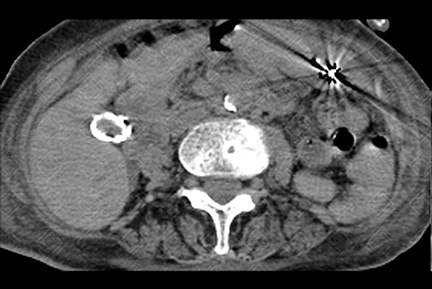

Texto alternativo para a imagem Figuras 1 e 2. Créditos: Dra. Elazir Mota - Rio de Janeiro/RJ

Descrição das figuras 1 e 2: Tomografia computadorizada de abdome evidenciando calcificação grosseira e concêntrica, envolvendo a parede da vesícula biliar (seta vermelha), caracterizando a clássica vesícula em porcelana.

• Radiografia convencional e tomografia computadorizada do abdome: As imagens são semelhantes, com a presença de halo de mineralização envolvendo a parede da vesícula biliar ( figuras acima );